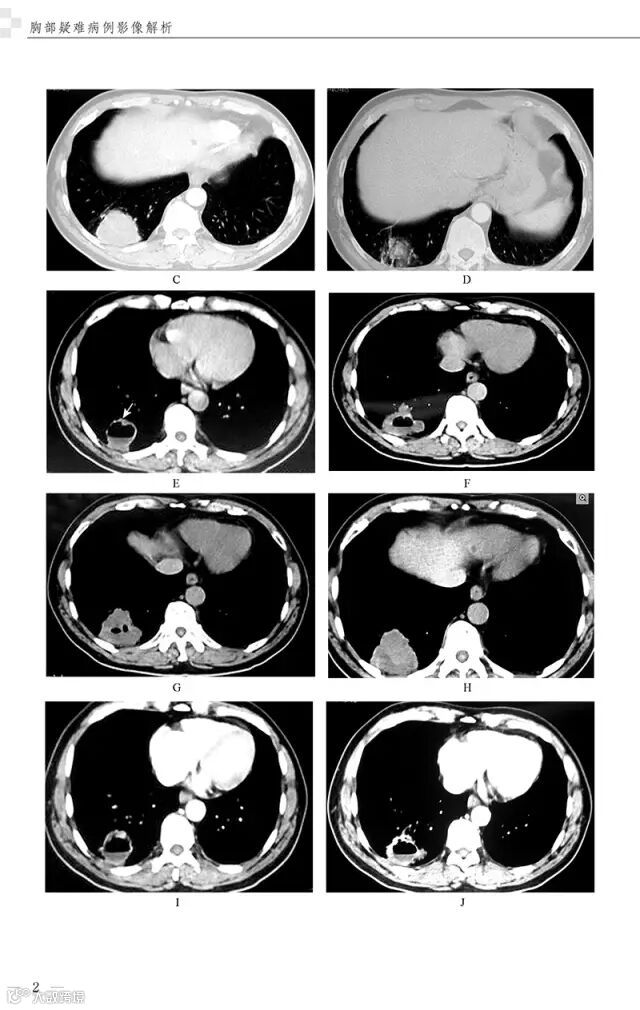

精彩插图

病例2 后纵隔脂肪肉瘤3